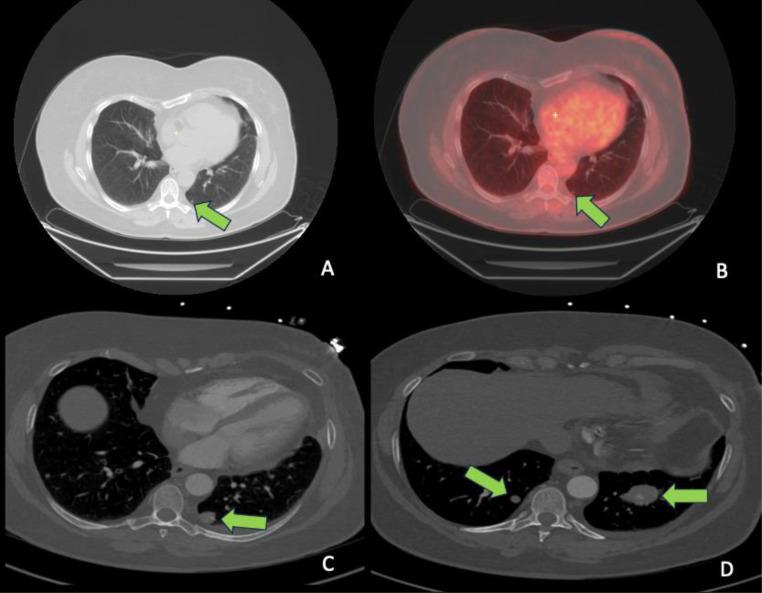

Metaplastic breast carcinoma is rare and may present as a highly aggressive subtype of breast cancer. In this case report of metastatic metaplastic breast carcinoma with osteosarcomatous differentiation in a female patient previously treated for invasive ductal carcinoma, we describe the new presentation of a palpable mass with associated calcifications on imaging near the site of prior partial mastectomy. This article will detail the clinical presentation, imaging findings, histopathology, and clinical course following treatment of our case. Knowledge of the clinical and imaging presentation of this rare subtype, which can present with benign features on mammography and ultrasound, can facilitate timely diagnosis as treatment paradigms evolve.

化生性乳腺癌较为罕见,可能是一种侵袭性很强的乳腺癌亚型。在本病例报告中,一名曾接受浸润性导管癌治疗的女性患者发生了具有骨肉瘤分化的转移性化生性乳腺癌,我们描述了在先前保乳手术部位附近出现可触及肿块并伴有影像学钙化的新表现。本文将详细介绍我们病例的临床表现、影像学检查结果、组织病理学以及治疗后的临床病程。随着治疗模式的发展,了解这种罕见亚型在乳腺X线摄影和超声检查中可能表现出良性特征的临床和影像学表现,有助于及时诊断。